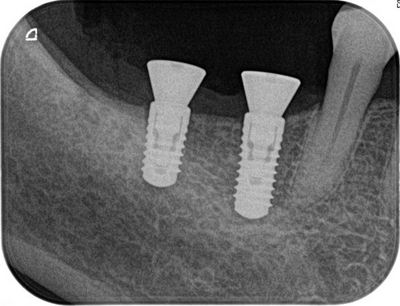

オペ終了時のレントゲン写真です。

Y・Mさん、2本のオペお疲れ様でした。

咬める日が楽しみです!